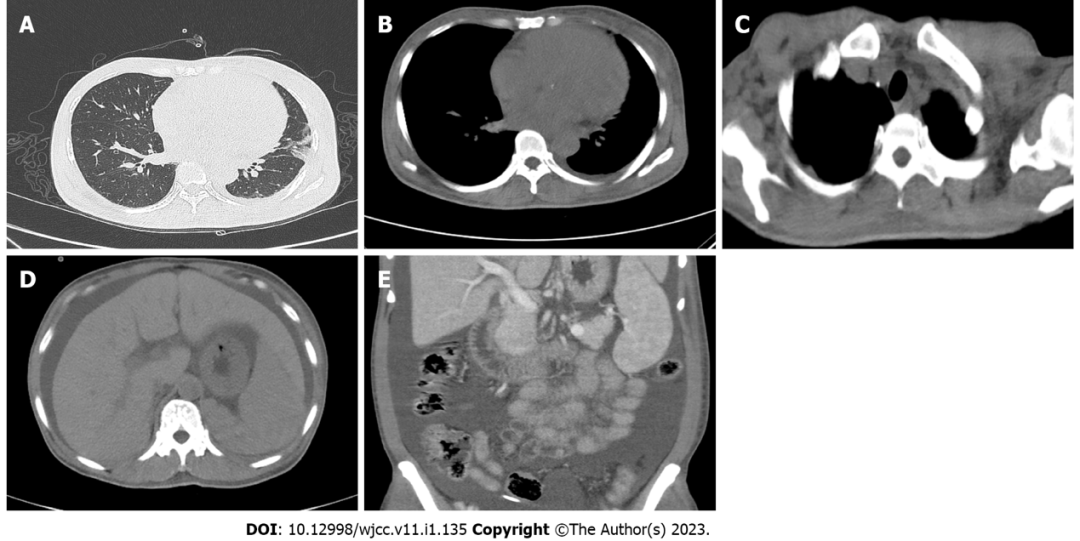

当时行胸腹部增强CT示: 1)左肺上叶舌段、双肺下叶条片、条索影,考虑炎性改变伴陈旧性病灶; 2)心脏饱满;双侧胸膜稍增厚,左侧胸腔少量积液; 3)纵隔及双侧腋窝多发淋巴结显示,部分肿大; 4)可疑肝硬化,脾大,腹盆腔积水; 5)胃肠道壁肿厚,腹盆腔内脂肪间隙模糊(图1)。

图1. 2021年3月16日胸部和腹部CT

A:左肺舌段和双肺下叶的炎症性病变,双侧胸膜略微增厚,左胸腔少量积液;B:心脏轻微增大,纵隔淋巴结增大;C:双侧腋窝淋巴结增大;D:肝裂变大和腹水;E:脾肿大、盆腔积液、肠壁肿胀增厚,腹部和盆腔脂肪间隙模糊